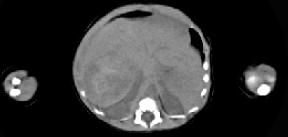

男,5天,上腹部膨隆,CT所见如图,最可能的诊断是 ( )A、肝脓肿B、肝转移瘤C、肝母细胞瘤D、肝血管瘤E、原发性肝癌

问题 男,5天,上腹部膨隆,CT所见如图,最可能的诊断是 ( )

选项 A、肝脓肿 B、肝转移瘤 C、肝母细胞瘤 D、肝血管瘤 E、原发性肝癌

答案 C